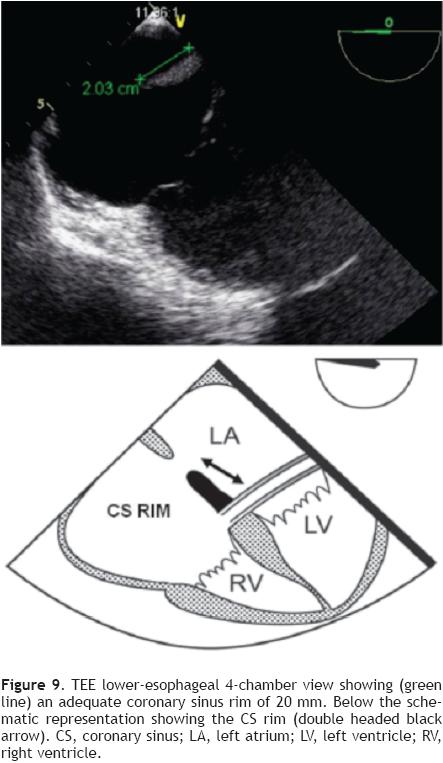

Measurement of the CS rim (Figure 9) requires a lower esophageal position, near or at the level of the gastroesophageal junction at 0°, where the CS will be seen on the right of the monitor screen. It is necessary to perform a slight retroflexion of the probe to obtain a view of both the lower end of the ASD and the CS.